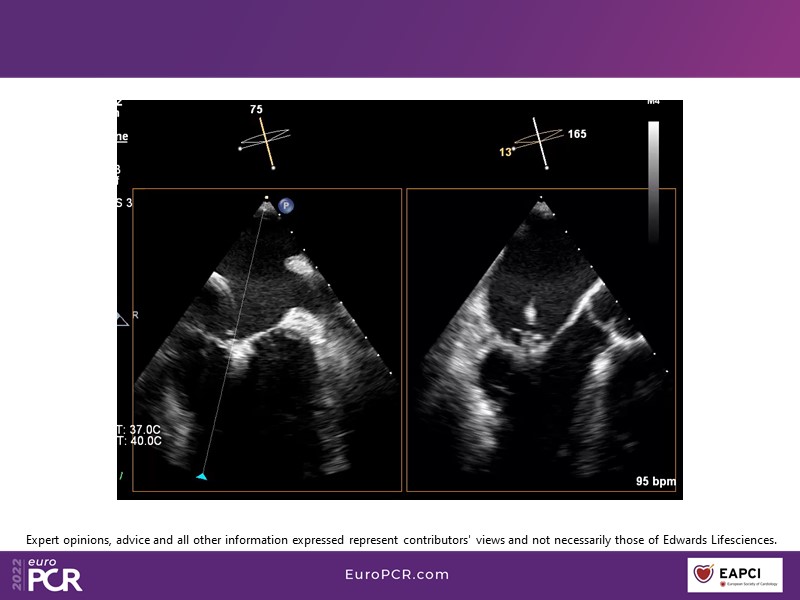

With study outcomes and clinical cases, this EuroPCR 2022 session will enable you to discuss the anatomical considerations that define suitable candidates for treatment of mitral regurgitation with the PASCAL platform and highlight key differentiators and tips and tricks for its use.

- To discuss which anatomical considerations define suitable candidates for the treatment of mitral regurgitation with the PASCAL platform

- To attend case-based discussions that will highlight key differentiators and tips and tricks when using the PASCAL platform to treat mitral regurgitation